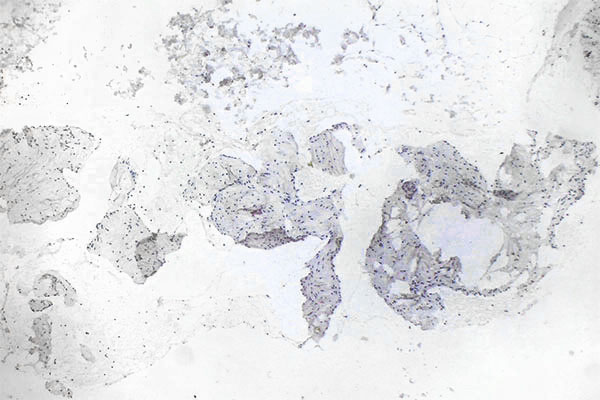

Histopathological section; CD31 stain for specific staining of vascular endothelial cells, which then stain dark brown. 80x magnification of the punch cylinder. This proves that the outer cellular boundary of the visible lesion corresponds to blood vessel endothelia.

Histopathological section; immunohistological staining using MIB-1 for the Ki67 antigen is a classic stain to show the proliferation activity of a lesion. As a proliferation marker, Ki67 indicates all cells undergoing cell division in the broadest sense (outside the G0 phase in the cell cycle). Here, only very few actively dividing nuclei (here without mitotic spindles) are detectable as positive nuclear staining. Thus, a very low proliferation rate is an indication of a benign lesion.

Immunohistochemical staining with CD31 (blood vessel endothelium) lining the lesion, and the irregular, sometimes patchy, asymmetric surrounding of smooth muscle cells (SMA stain) as well as evidence of atypical collagen and elastic fibers (EvG stain) distributed in the venous vessel wall make the diagnosis highly probable. Venous malformations show little proliferative activity (MIB-1). The histopathologically very similar-looking lymphatic malformation can be well differentiated by D2-40 (podoplanin) staining, which specifically stains only lymphatic vessel endothelia.